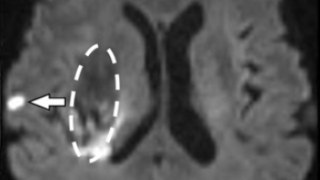

しかし、がんゲノム医療では、検出された遺伝子の変異に対して、医学論文に書かれた過去の症例を参考に治療方針を検討するため、専門の医師はデータベースから該当しそうな論文を一つ一つ検索し、患者に適した治療法や治療法ごとの効果などを解読する必要があり、この作業に多大な時間がかかります(図1)。そのため、2018年4月に富士通研究所は、東大医科研と、がんゲノム医療における専門の医師の作業をAIによって効率化・高度化するための共同研究を開始し、このたび共同研究で開発した技術を活用した実証実験により効果を確認しました。

図1 がんゲノム医療における治療方針の検討作業の位置付け